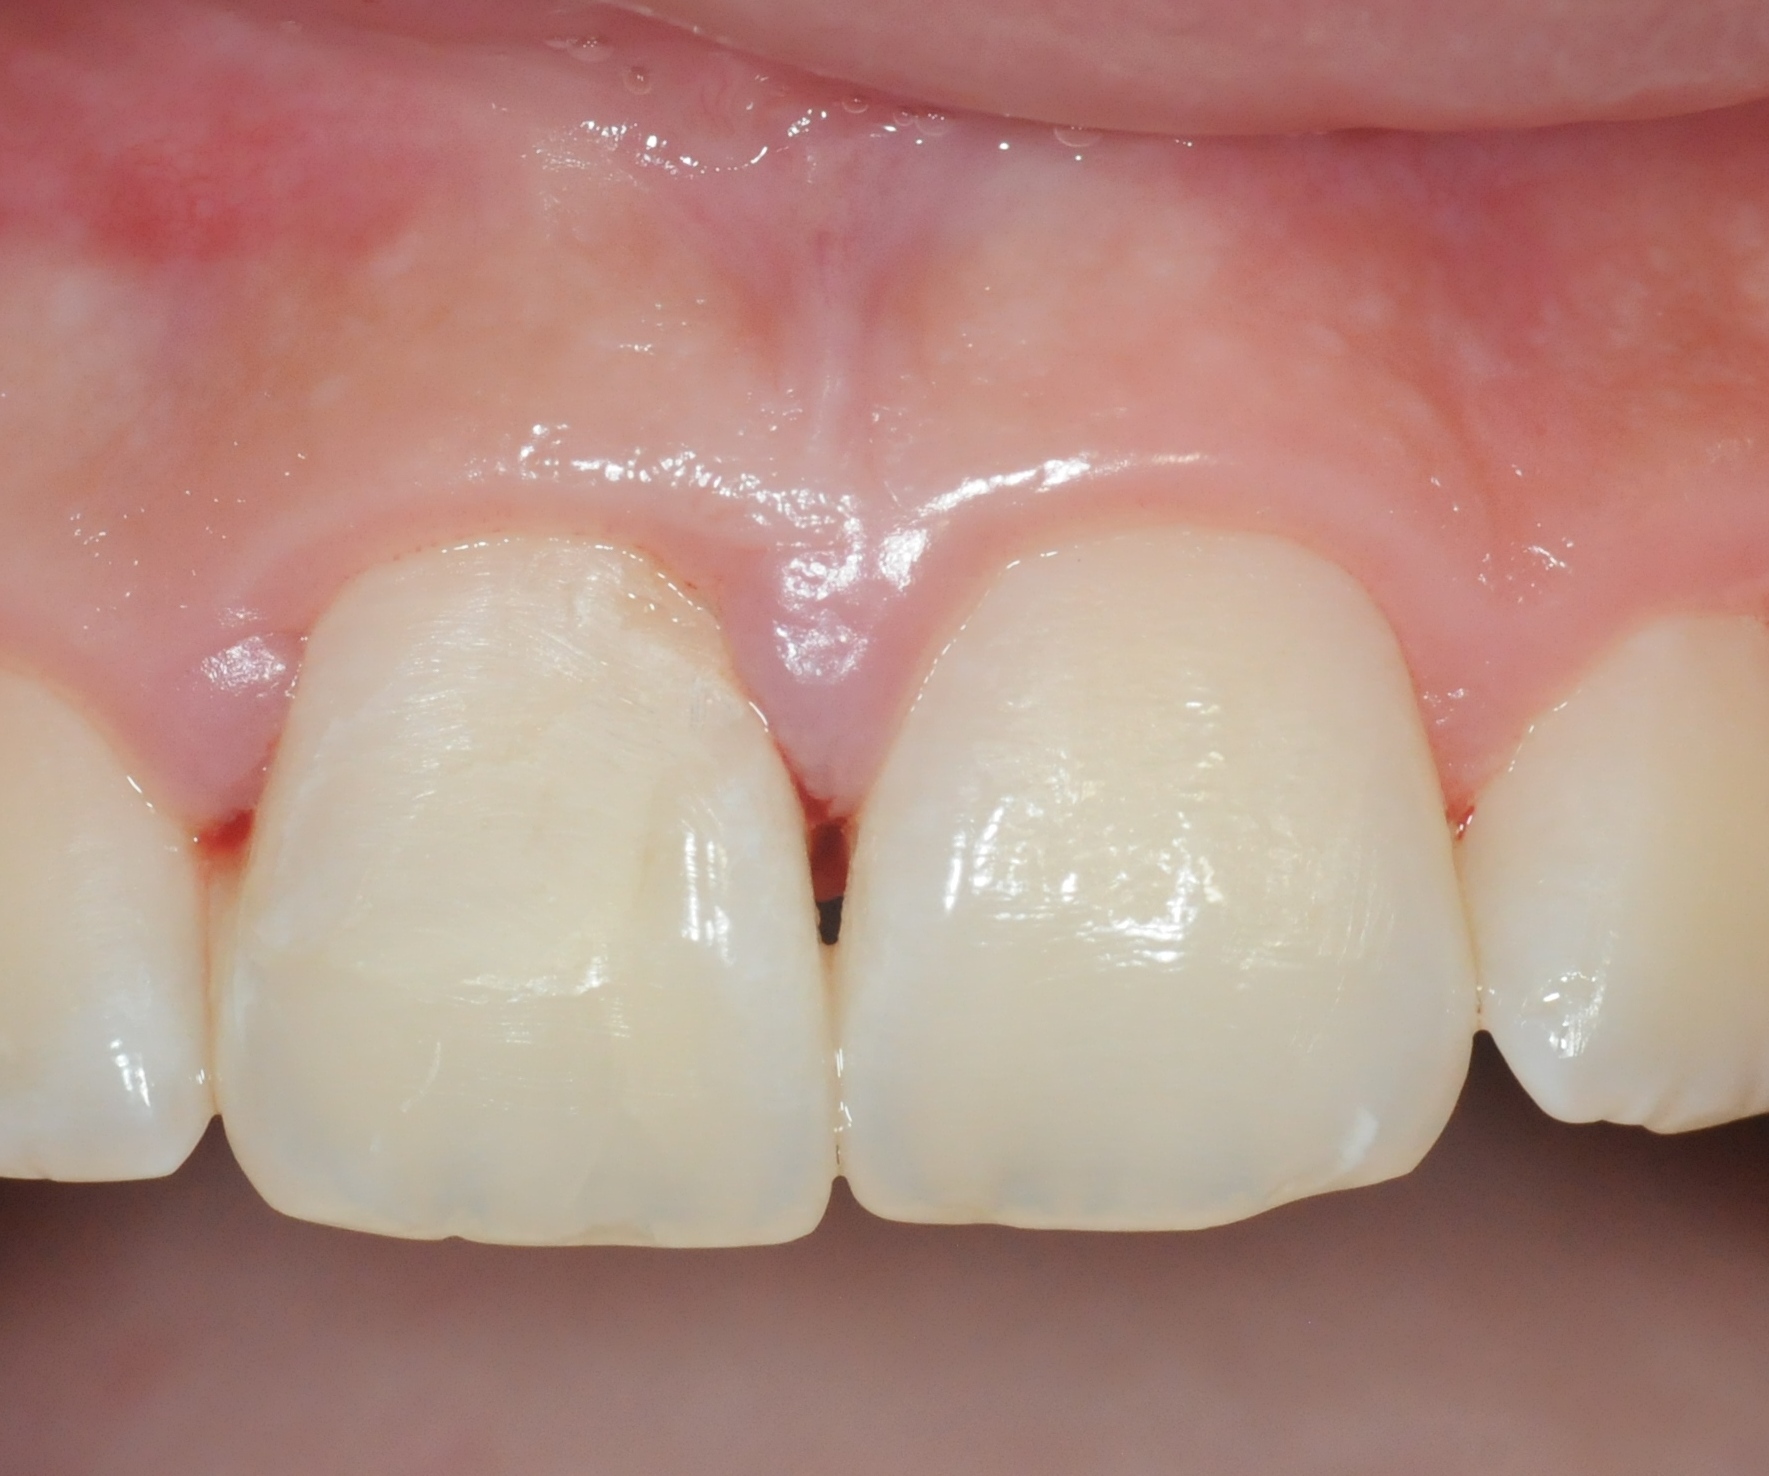

Zahnfraktur nach Fahrradsturz

Ein wirklich häufiger Unfall bei Kindern ist der Sturz, in dessen Folge ein noch sehr junger Zahn entweder frakturiert, also abbricht, oder gar ganz herausgeschlagen wird.

Im hier gezeigten Fall stürzte ein 13 jähriger Junge auf dem Schulweg mit dem Fahrrad. Dabei frakturierte der rechte obere bleibende Schneidezahn, wobei die Bruchlinie so unglücklich verlief, dass sie den Zahn-Nerv freilegte. Höchste Gefahr für den Zahn und Ursache für möglicherweise viele erfolglose Behandlungen mit schlussendlichem Zahnverlust, wenn hier nicht richtig und schnell gehandelt wird.

In diesem Fall war nur der rechte obere Schneidezahn ganz isoliert betroffen, der aufgrund des Traumas berührungsempfindlich und aufgrund des freiliegenden Nervs temperaturempfindlich war. Der Nerv ist deutlich zu sehen.